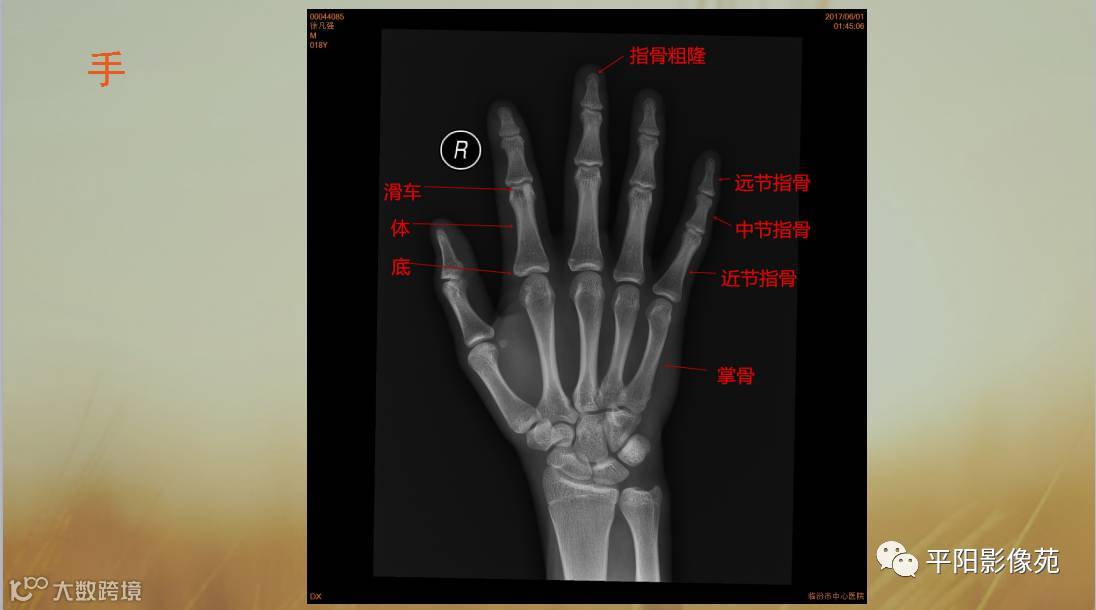

四肢骨骼X线解剖